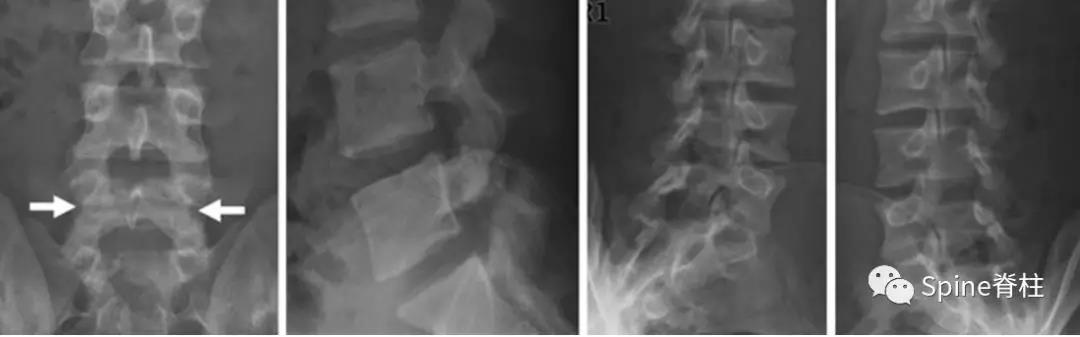

图:L5全椎板裂15岁相扑运动员,严重腰痛,后伸明显加重正侧位X线示椎板水平骨折线(白箭头)。MRI示T2椎板高信号,T1椎板低信号

图:L4全椎板裂16岁男孩,3年严重腰痛,后伸受限其中L5椎体骶化